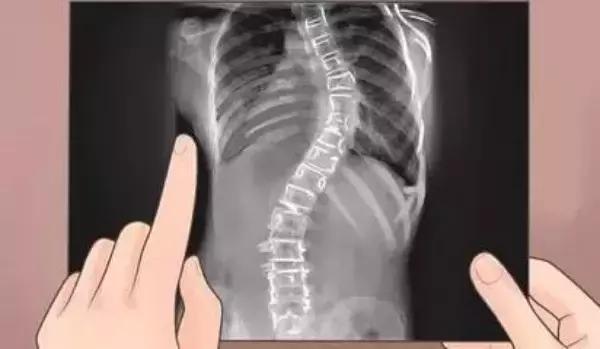

三、骨骼问题

母体骨骼问题,比如骨盆畸形和脊柱畸形,容易引发孕期早产。

骨骼畸形多由身体内部气血不足造成,所以此类女性多伴有气血不足,体质虚弱等身体状况。

孕康备孕中,建议此类女性先行治愈骨骼问题,再考虑孕育下一代。

脊柱侧弯多发在女性青少年阶段,这也是孕康备孕体系中主张的,备孕从小开始,从发现孩子骨骼问题开始,家长就该认识到这对于孩子将来孕育能力和风险的影响。

孕康备孕体系中,有专门针对脊柱侧弯康复的部分,有进一步了解需要的,请联系暖宫瑜伽。